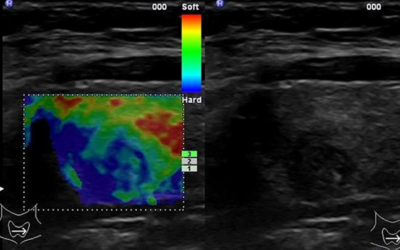

Ultraskaņas elastogrāfija

Ultraskaņas elastogrāfija ir neinvazīva attēlveidošanas metode, ko pielieto, lai noteiktu relatīvo audu saspiežamību...